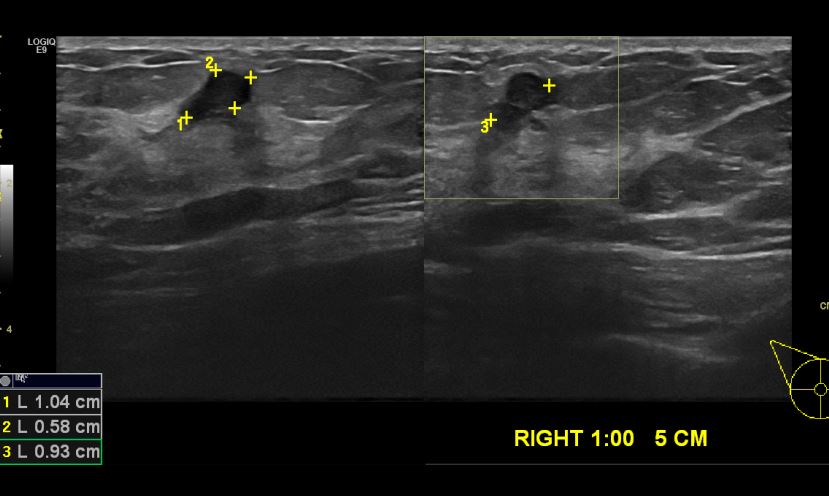

상기 환자 건강검진상 이상 소견으로 내원한 60대 여성분으로 우측 1시 방향에서

5cm 떨어진 거리에 있는 으심스러운 혹 조직검사 시행하여 우측 침윤성 유관암 진단 되었습니다.